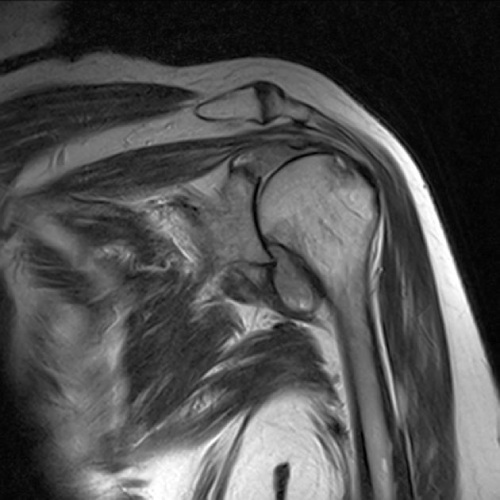

Hình ảnh chụp MRI viêm khớp dạng thấp

Phương pháp chụp MRI cho phép bác sĩ quan sát chi tiết hơn tình trạng khớp, dây chằng, gân và cơ quanh khớp. Các hình ảnh viêm khớp dạng thấp được thể hiện qua chụp MRI.

Hình ảnh mòn dọc điểm bám bao khớp

Phát hiện khớp bị mòn dọc theo điểm bám của bao khớp – dây chằng với phần thủng ở khớp vai, phì đại bao hoạt dịch khớp ở bệnh nhân viêm khớp dạng thấp. Ảnh: Radiopaedia